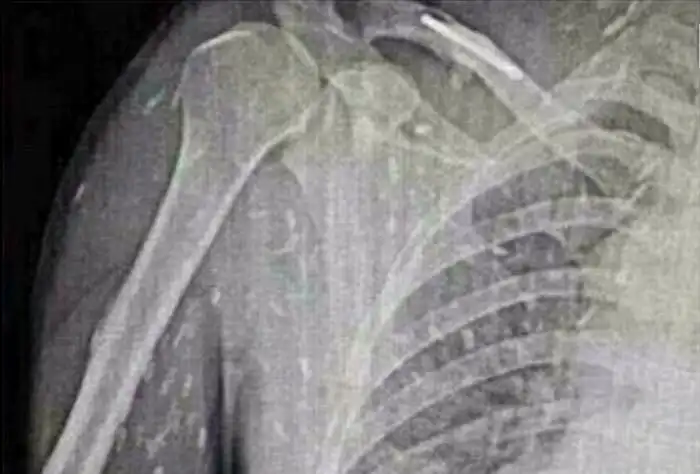

Смотрим далее, что произошло с одной девушкой из Китая, которая отобедал некачественными суши. Она почувствовала, что с ней что-то не так только спустя несколько дней и обратилась в больницу. Из-за жалобы на боли в животе, врач назначил ей рентген, который показал ужасающие результаты. Весь её организм подвергся заражению паразитами. К счастью, с пострадавшей девушкой теперь все в порядке, ведь в подобной ситуации главное - это быстро отреагировать на первые симптомы.